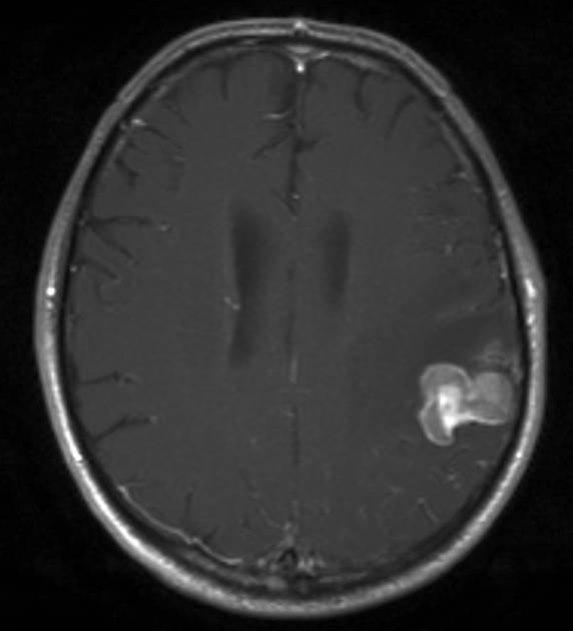

MR er den mest sensitive undersøkelsen såvel til påvisning av små metastaser som til å påvise andre sykdommer i hjernen. Ved CT av hjernen med kontrast finnes multiple hjernemetastaser hos ca. 50 prosent, ved MR-scanning hos ca. 75 prosent.

De hyppigste primærsvulstene er lungekreft, brystkreft, malignt melanom, nyrekreft og tykktarms-/endetarmskreft. Cirka 85 prosent av hjernemetastasene finnes i storhjernen og 15 prosent i lillehjernen og hjernestammen. Hos cirka ti prosent av kreftpasientene er sentralnervesystemet eneste sted hvor spredning påvises, hos resten er det metastaser andre steder i kroppen. Tre av fire pasienter med spredning til hjernen har flere eller mange metastaser i hjernen.